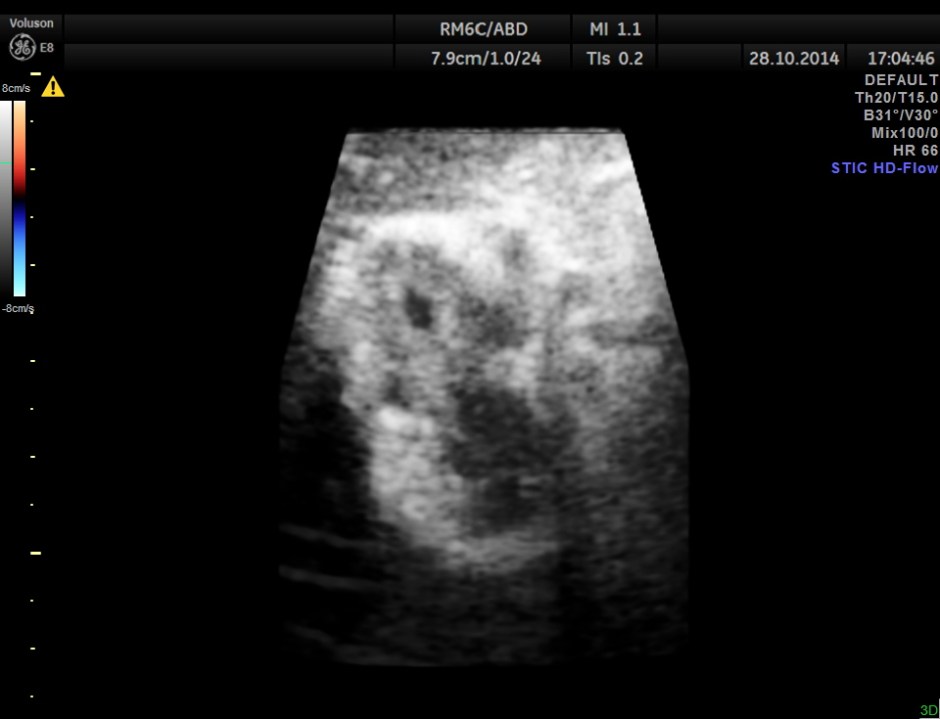

Ultrasound examination revealed the following findings :

Hypo echoic linear spaces are seen around the gallbladder.

STIC HD flow image.